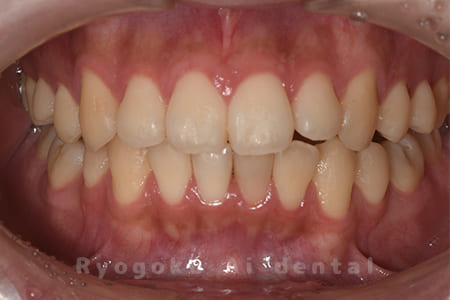

前歯の腫れが治らない、とのことでご来院された患者様です。前歯には他院で自費で入れた被せ物が入っており、被せ物のやり変えと共に根管治療の提案を致しましたが、このままの状態での治療を希望されたため、歯根端切除術を行いました。手術後の痕も気にならずに、腫れもなくなり、非常に満足して頂きました。半年経過を追っておりますが、現在も再発等ございません。

<リスク・副作用>

外科手術のため、術後に出血、痛みや腫れ、違和感を伴います。口腔内の状態によっては適応できないことがあります。歯根端切除で治らなければ抜歯を検討しなくていけない場合もあります。